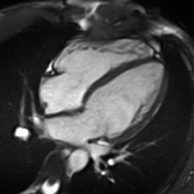

MRI sequences of a cardiac myxoma (a benign tumor)[1]